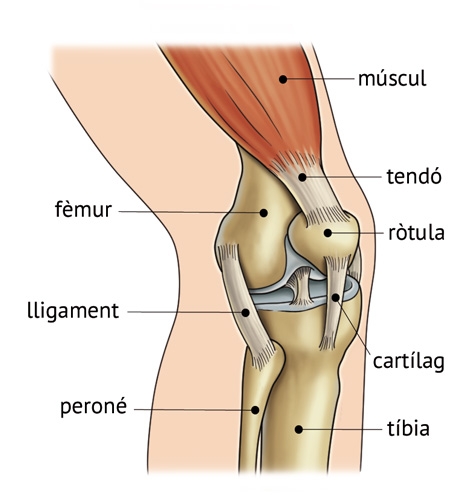

Els extrems de molts ossos de l’esquelet estan coberts de cartílag, que és un teixit molt més flexible i tou que el teixit ossi que forma els ossos. També hi ha cartílag en altres zones del cos, com el nas i les orelles.

Els ossos de l’esquelet s’uneixen entre si mitjançant les articulacions. El genoll i el muscle són articulacions mòbils i els ossos respectius es mantenen units mitjançant elslligaments.